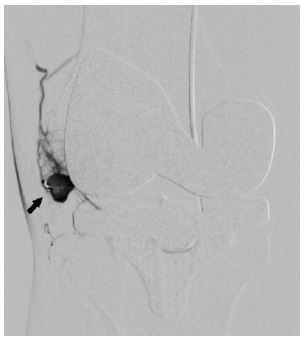

In view of continued knee joint swelling, the patient underwent right lower limb angiography the following week through the right femoral artery approach which identified a Pseudoaneurysm arising from the inferior medial genicular artery. This was embolized using 250 microns’ particles- embospheres and 2mm push able coils. Selective angiogram performed from superior medial and lateral genicular artery showed abnormal blush and pruning was done using 250-micron embospheres (Figures 3,4 & 5). An Ice pack was placed over the knee while instilling embolic agent particles to cause vasoconstriction of the skin arterial supply to avoid ischemia.

Figure 3: Angiography done through catheter in popliteal artery shows pseudoanuerysm (Solid arrow) arising from inferior medial geniculate artery (thin arrow).